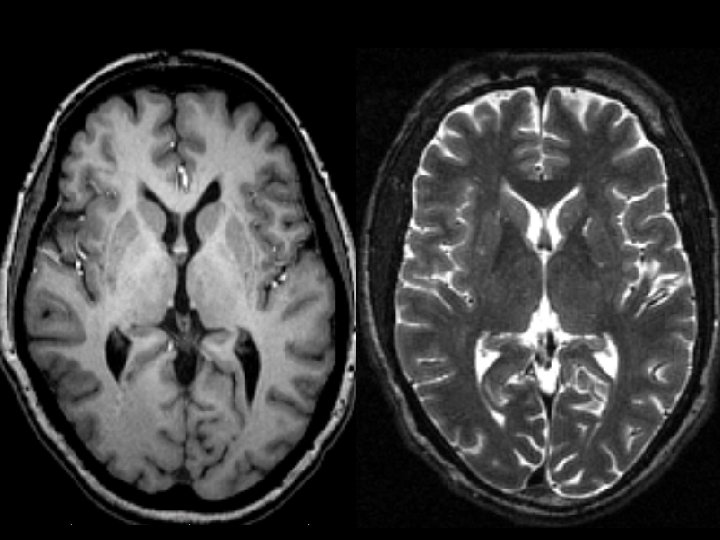

Normal MRI T 1 Weighted Normal MRI T 1 Weighted

Normal MRI T 2 Weighted Normal MRI T 2 Weighted